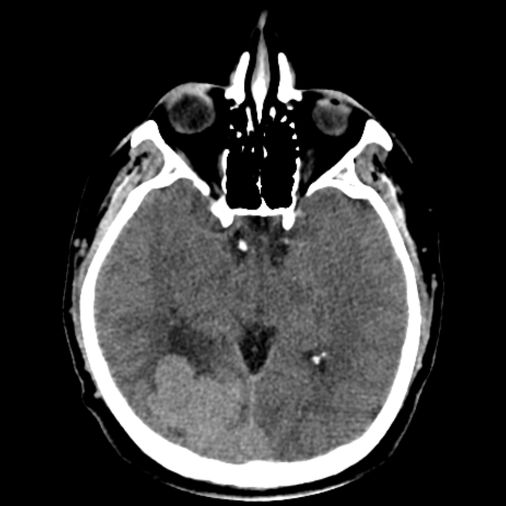

44 yaş, E

Baş ağrısı

Lenfoma

hemorajik glioblastoma multiforme (GBM, WHO Grade 4)